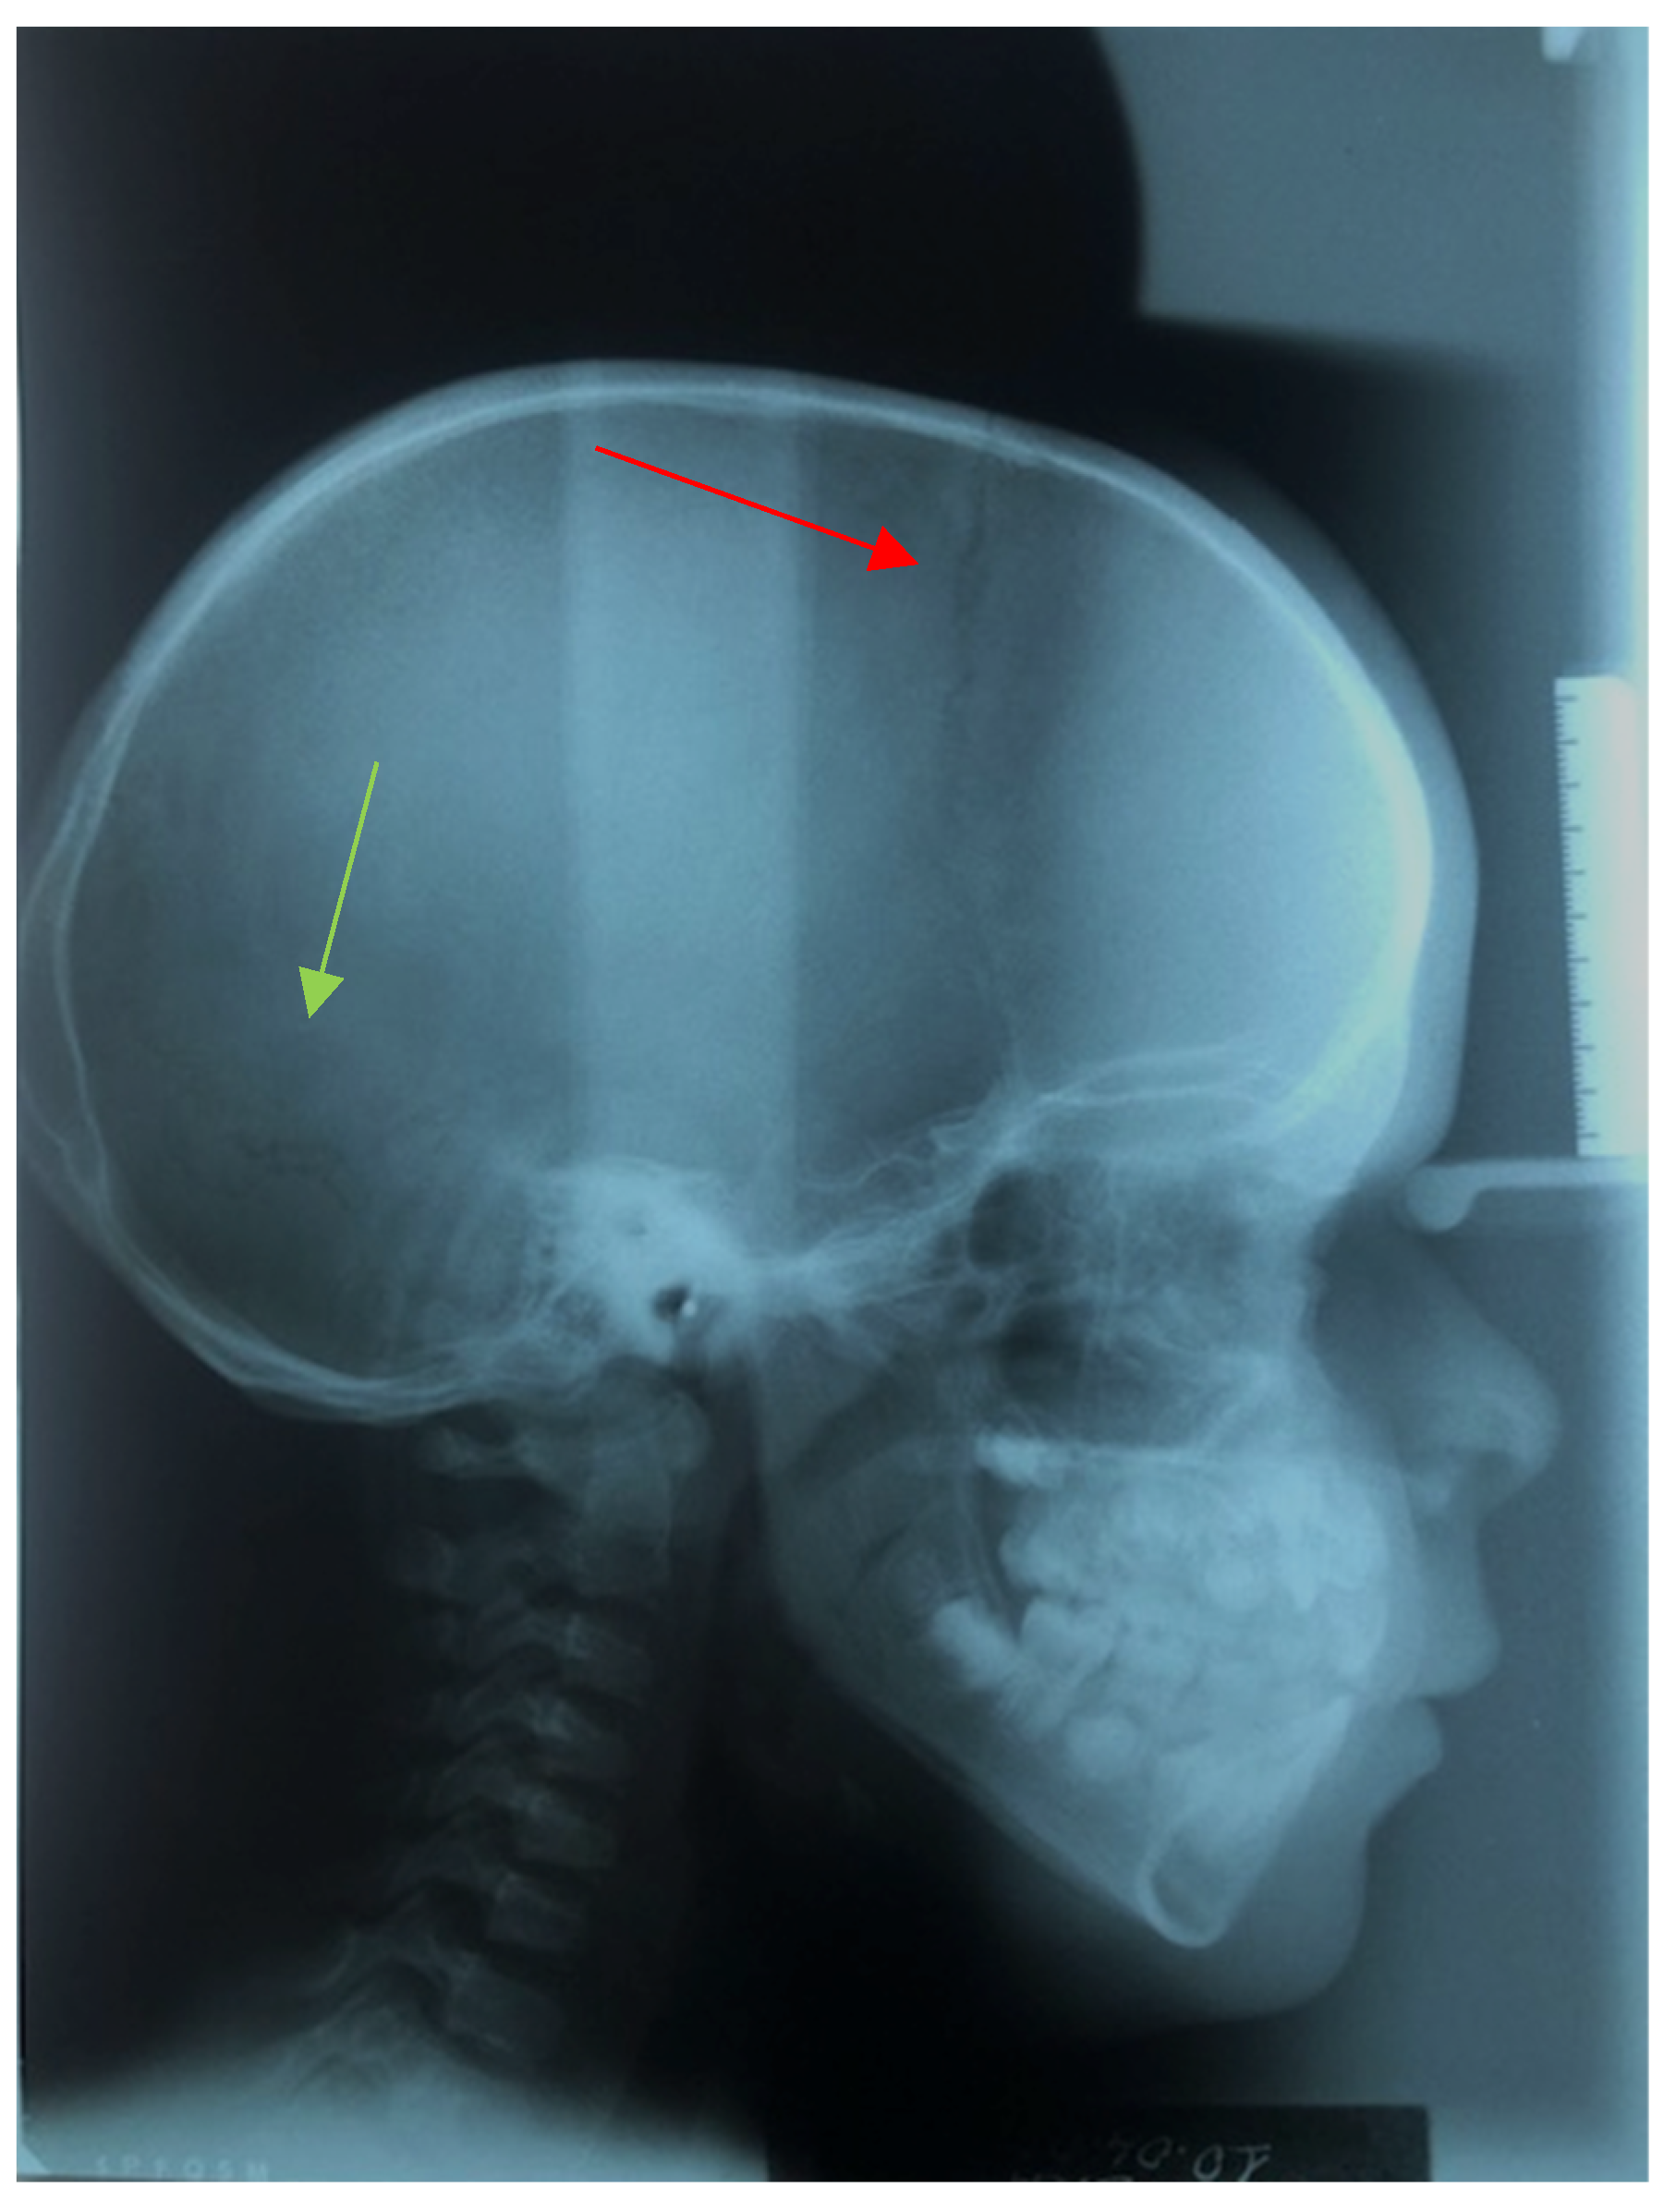

2.1. Cephalometric Analysis